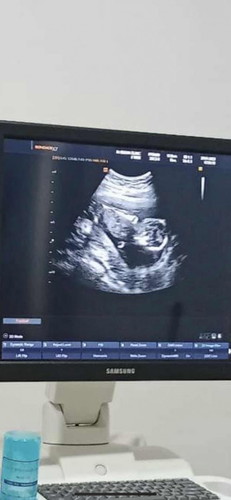

14สัปดาห์5วัน

14สัปดาห์5วัน แม่ๆบ้านไหนอายุครรภ์ประมานนี้รู้เพศกันแล้วบ้างค่ะ บ้านนี้มองไม่ค่อยออกเลยค่ะแต่คุณหมอบอกเพศหญิง70% เพราะไม่แพ้ท้องเลยแต่ต้องรอเดือนหน้าอีกที

ต้องรอดูไปเรื่อยๆ ค่ะ ให้น้องโตกว่านี้ เราตรวจnipt รู้ตั้งแต่ 12 วีค แล้วน้องอ้าโชว์ด้วย ผู้ชายจะเห็นเร็วกว่าผู้หญิงเพราะมีอะไรยื่นออกมาค่ะ ส่วนตัวไม่แพ้ท้องเลยค่ะ

ของเรา14 w 4d ไม่แพ้ท้องเลยเหมือนกันค่ะ หมอโทรมาแจ้งผล nift เมื่อวาน เพศชาย 99.9%ค่ะ😀